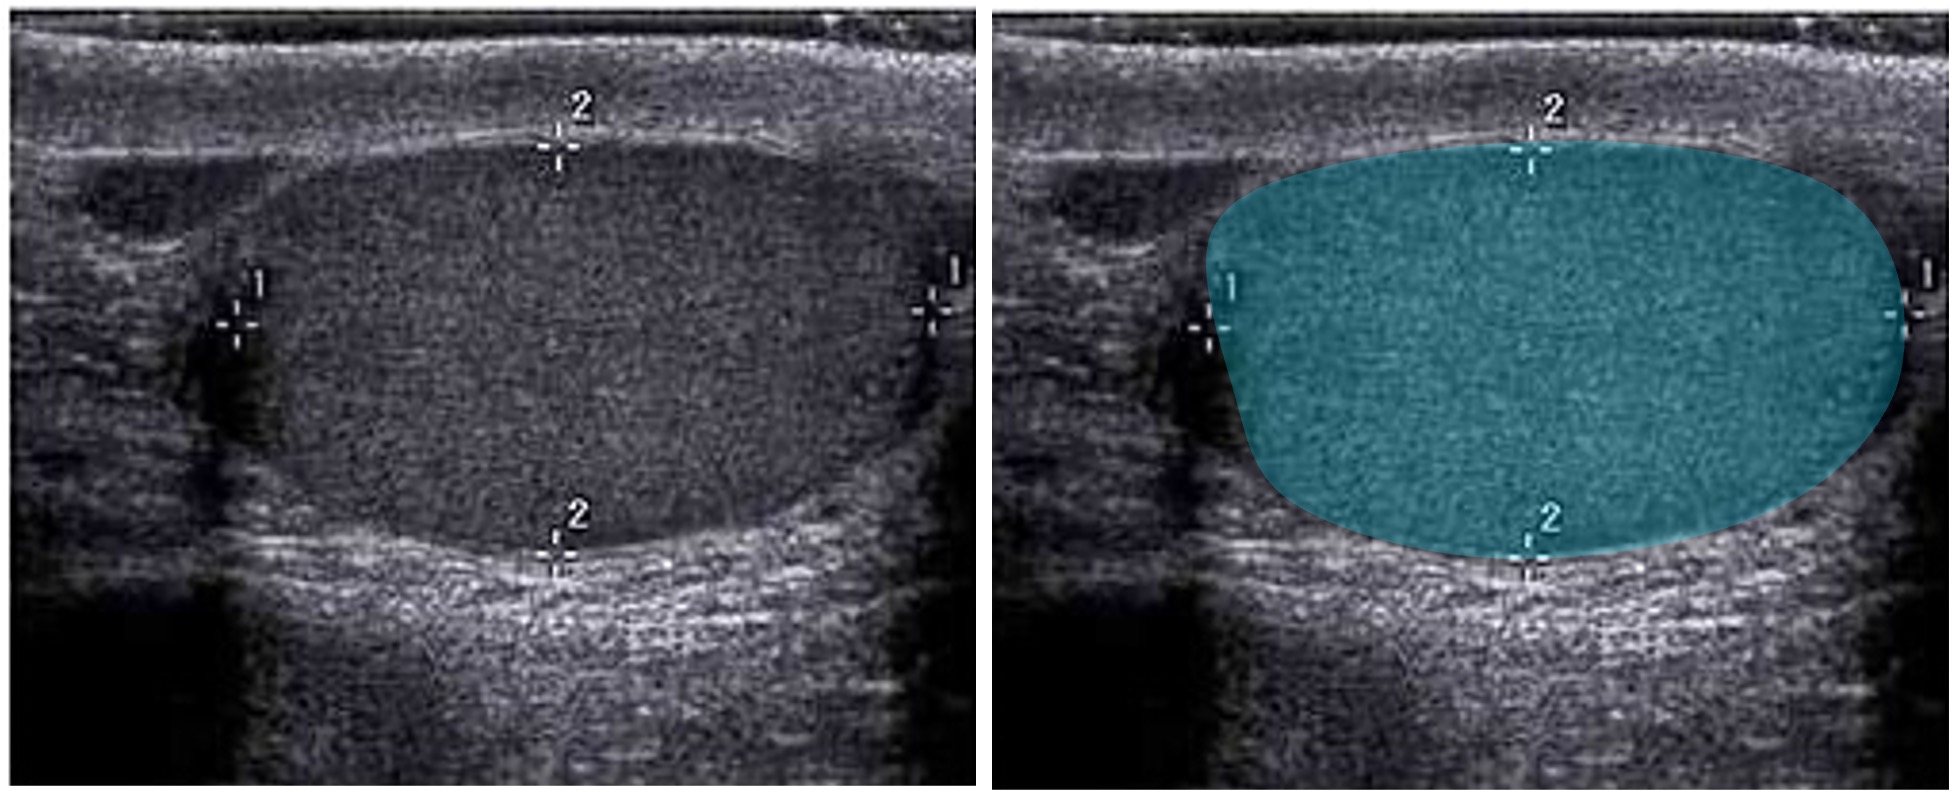

Sonografie der Hoden

Durchführung

- Hierfür eignet sich am besten ein flacher Linearschallkopf

- Patent liegt auf dem Rücken

- Untersuchung in längs (Longitudinal-) und quer (Transversalebene) im direkten Seitenvergleich

Befundung

- Form: oval

- Größe: 4–5 cm lang, 3 cm breit und 2–3 cm dick

- Volumen: 15-25 ml und kann analog zur Restharn-Formel berechnet werden (s. Sonografie der Niere und Harnleiter

) - Echogenität: echohomogenes Hodenparenchym

Pathologie

- Fehlbildungen, Raumforderungen, Hodentorsion

, Anomalie, Krampfadern (Varikozle) - Echofreie Areale deuten auf Flüssigkeitsansammlungen hin, wie eine Hydrozele oder Zyste

Chee-Wai Mak and Wen-Sheng Tzeng, CC BY 3.0, https://creativecommons.org/licenses/by/3.0, via Wikimedia Commons. Die Abbildung ist ein Derivat der oben genannten Abbildung. Das Bild wurde zugeschnitten, dupliziert und das Overlay ergänzt.